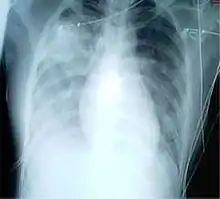

Chest X-ray of a pneumonia caused by influenza and Haemophilus influenzae, with patchy consolidations, mainly in the right upper lobe (arrow)